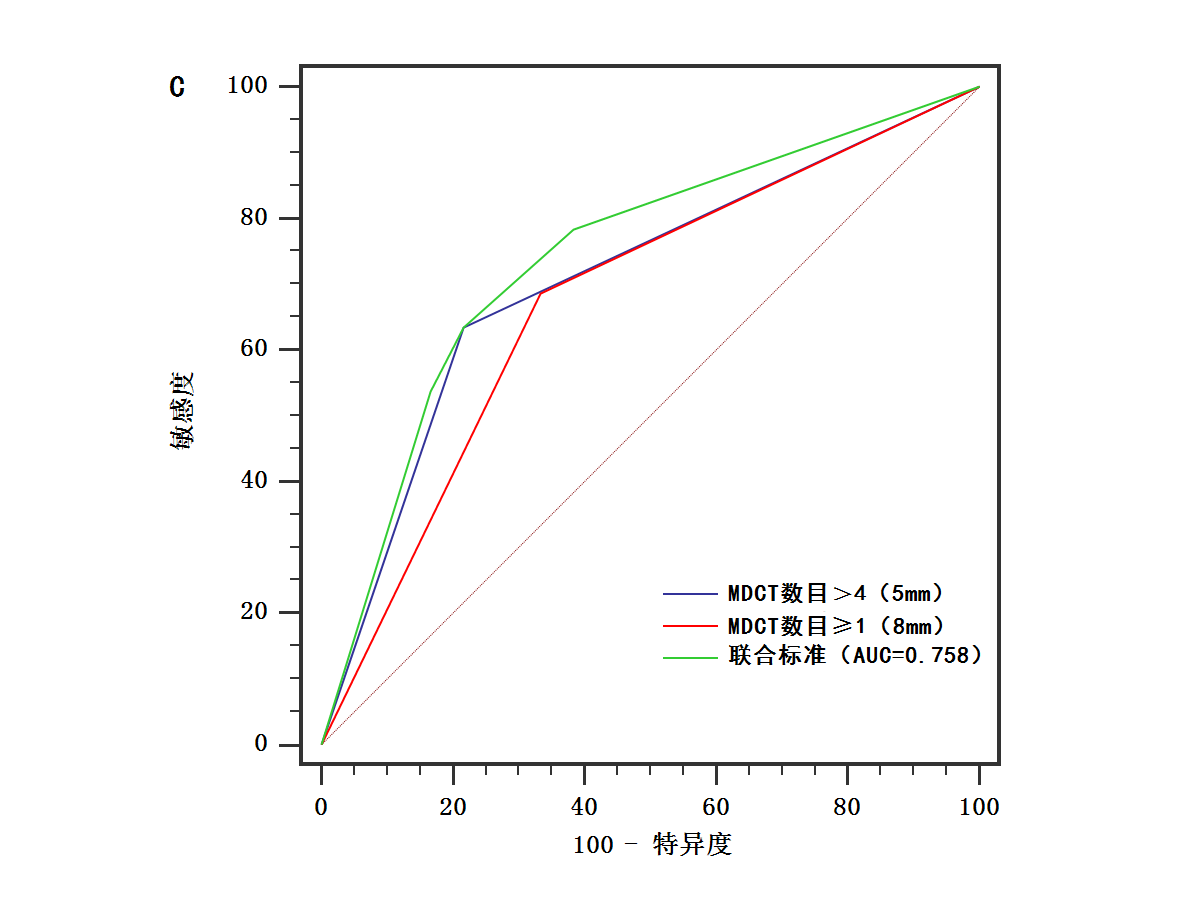

当以直径 5mm 为阈值时 MDCT 淋巴结数目>4���,直径 8mm 为阈值时 MDCT 淋巴结数目≥1 可作为辅助诊断指标���,术前诊断胃癌患者淋巴结转移是否存在�����。两指标的诊断性能是相当的����,当联合二者作为诊断标准时����,诊断准确度与敏感度提高��。

图2 不同大小标准的MDCT淋巴结数目以及二者联合标准诊断胃癌淋巴结转移的ROC曲线图